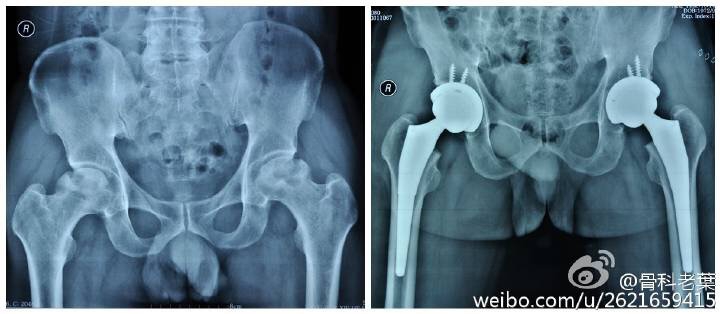

股骨头坏死可以根据病情,由轻到重分为六期,不同的时期有不同的治疗方法。

另附典型病例若干: